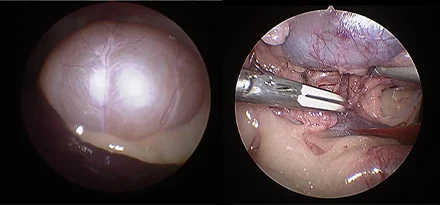

관절경

개,고양이 들은 다양한 관절질환이 존재하고, 복합적으로 존재하는 경우도 빈번합니다.

정확한 진단이 나지 않은 뒤 수술을 하게되면 증상개선이 더디거나 개선이 안될 수 있어, 정확한 진단이 필요합니다.

관절의 경우 X-ray 촬영등으로 진단의 한계가 명확하며, 상위 검사인 CT, MRI 촬영으로도 진단의 한계가 있습니다.

이때 관절경은 내부 구조물들을 직접 시각화 하여 보다 정확한 관절의 상태를 확인하고 진단할 수 있으며, 진단과 치료를 동시에 진행하는 경우도 있습니다. 대표적으로 십자인대단열(CCLR), 골연골염(OCD), 자뼈꿈치돌치유합부전(UAP), 내측관상돌기질환(MCD) 등에 활용될 수있습니다.

관절경 팔꿈치관절(Elbow) 확인

관절경 무릎관절(Stifle) 확인 (반월판 및 십자인대)